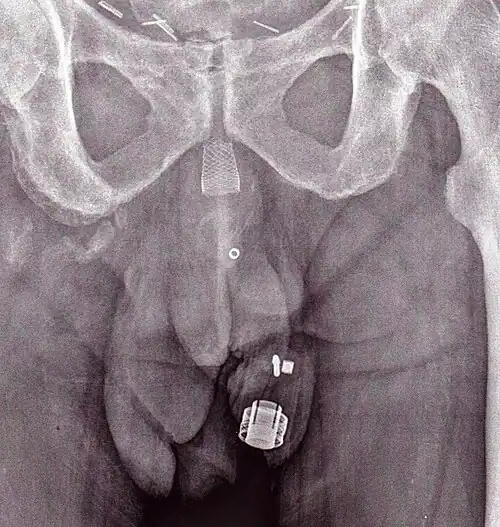

Image gallery

An X-ray image of implanted ZSI 375. The device is deactivated – the spring is compressed below the top of the cylinder. Patient is incontinent.